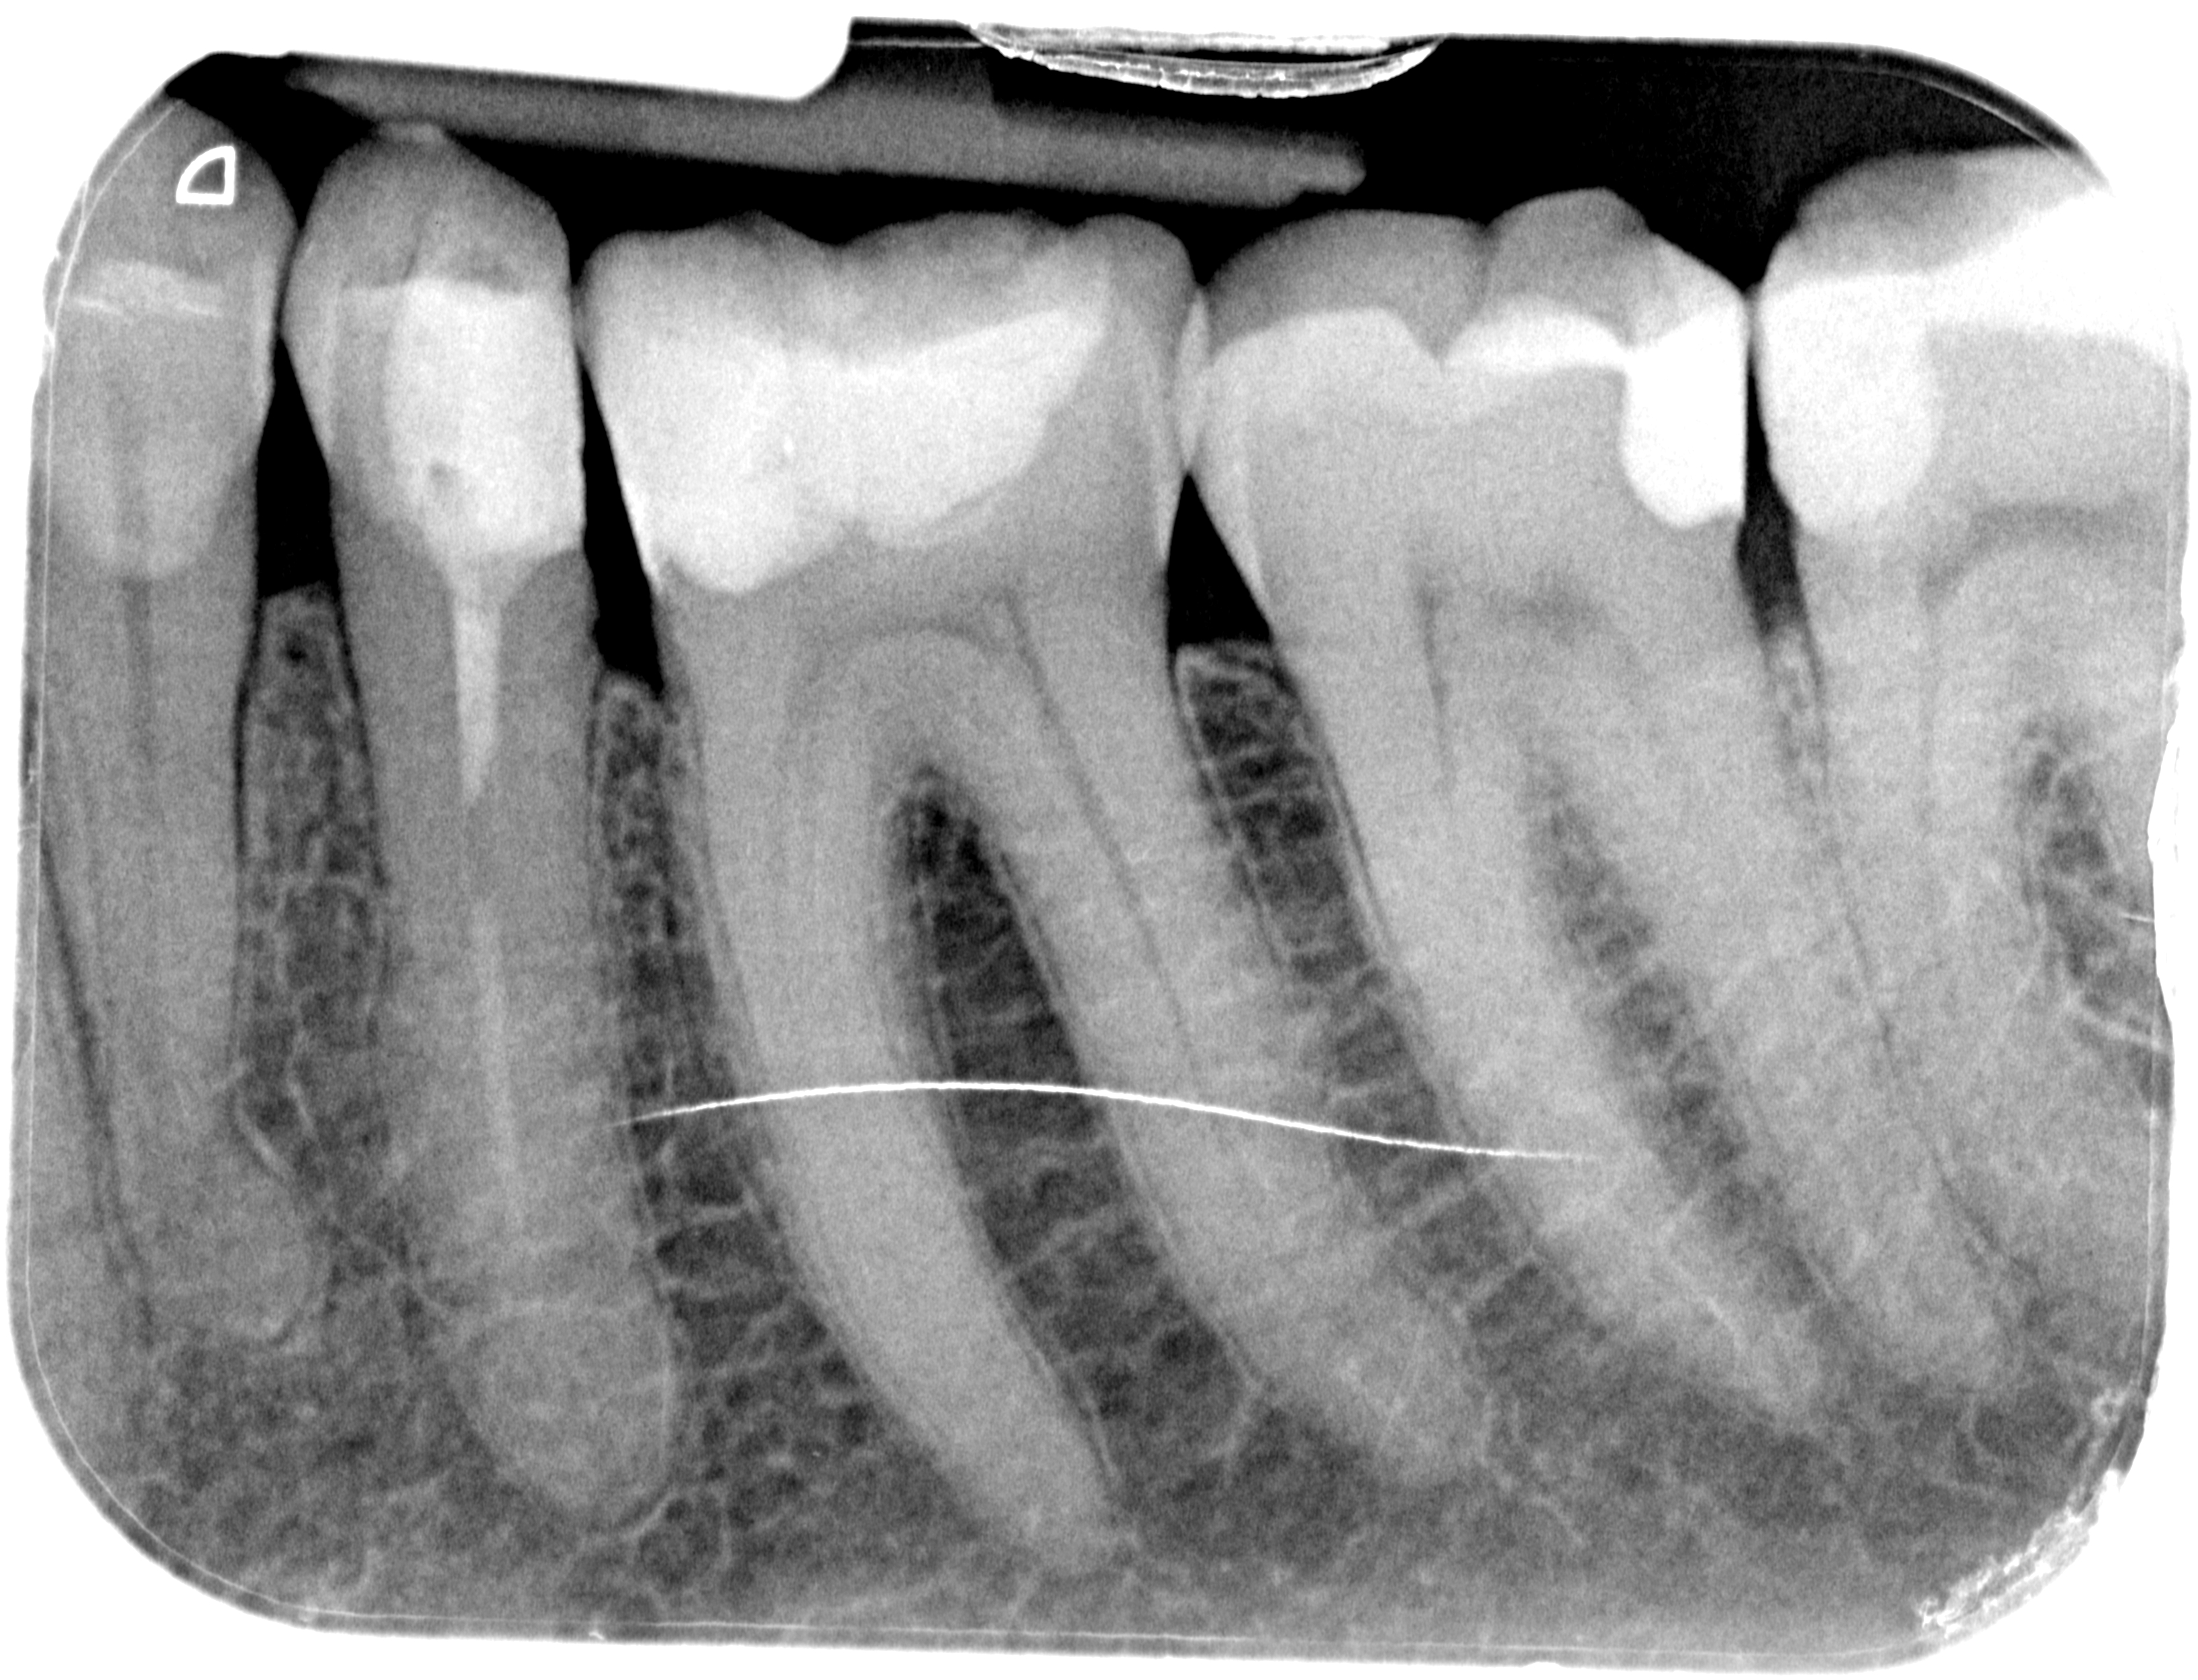

Prima

Presenza di otturazioni in amalgama.

Dopo

Sostituzioni delle otturazioni in amalgama con Intarsi in ceramica.